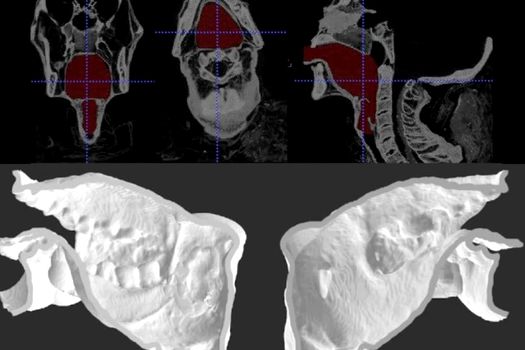

Au reuşit acest lucru cu ajutorul unui model 3D al aparatului respirator al preotului, conectat la un laringe artificial.

Acest proiect este primul de acest fel care reuşeşte cu succes să reproducă vocea unei persoane decedate, cu ajutorul metodelor artificiale. În viitor, cercetătorii speră să folosească modele computerizate pentru a reproduce propoziţii complete cu vocea preotului egiptean.

Sursa FOTO: Scientific Reports